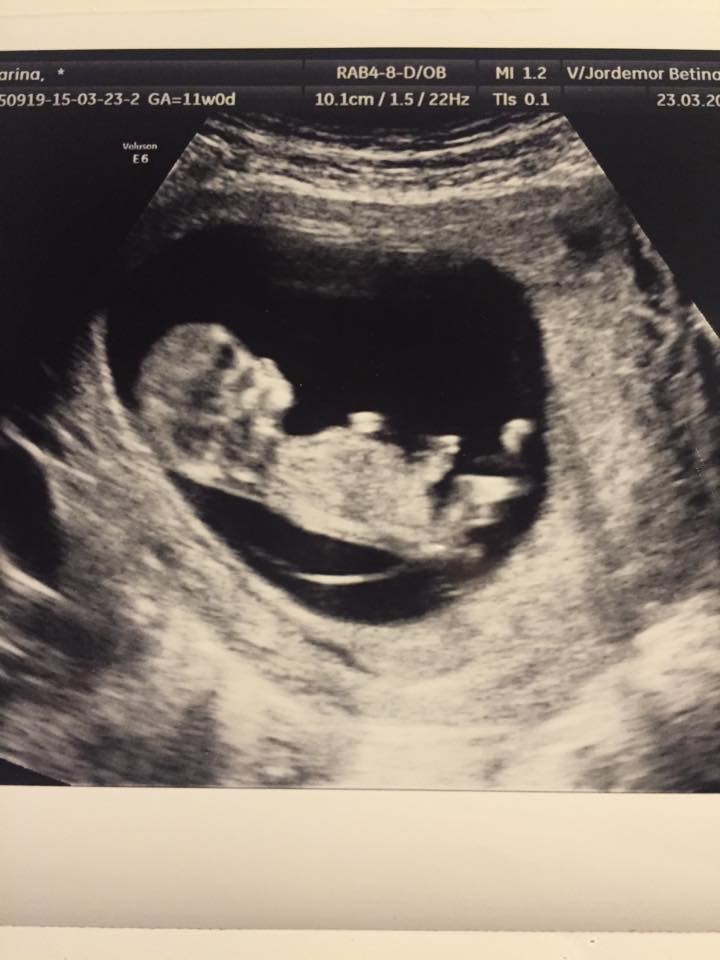

Da alle var samlet ved bordet, fik Clara en bonus gave, en lille ramme med et scannings billede af babyen.

I får lige et billede af baby, som i øvrigt så fin ud, havde 2 arme med 2 hænder og 5 finger, og 2 ben med fødder og 10 tæer. Hun målte i øvrigt foden fra tå til hæl - 7mm er sådan en lille fod på en baby der er 11+1 - meget småt og meget sødt